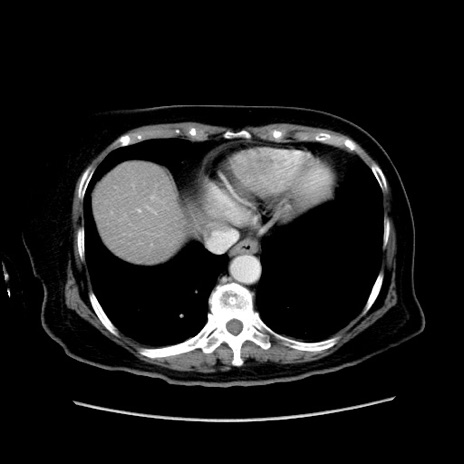

冠状断像

【症例】80歳代女性

【主訴】下腹部痛

【現病歴】約8時間前より下腹部痛の出現あり、救急外来受診。

【既往歴】両側付属器切除

【身体所見】意識清明、下腹部正中に手術痕あり、その部位に一致して圧痛と反跳痛あり。腸蠕動音は亢進。

【データ】WBC 9300、CRP 0.15